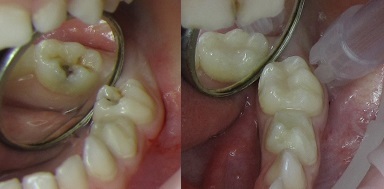

Пульпит молочных зубов: фото до и после